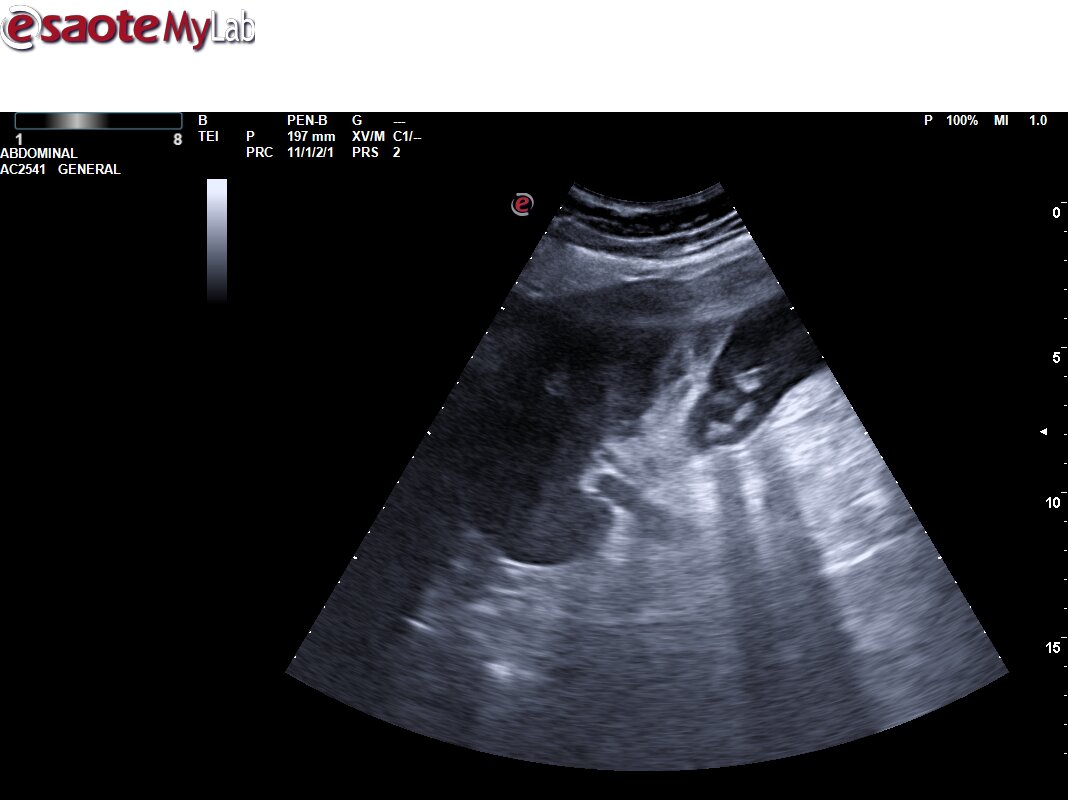

Ecografía Urgencias: Vesícula biliar de tamaño normal, con engrosamiento de la pared con edema de la mucosa. Pequeña colección perivesicular entre la pared vesicular y el reborde hepático de unos 10 mm de grosor, pérdida de continuidad de la pared vesicular compatible con pequeña perforación. Mínima lámina de líquido libre adyacente a la misma. Asocia también abundante contenido hiperecogénico en su interior en relación con barro biliar y varias litiasis en el infundíbulo vesicular. EcoMurphy +. Hallazgos sugestivos de colecistitis aguda complicada con colección / Abceso perivesicular. No líquido libre en los espacios abdominales explorados.

La paciente es intervenida al día siguiente del ingreso. Alta 24 horas después de colecistectomía laparoscópica.